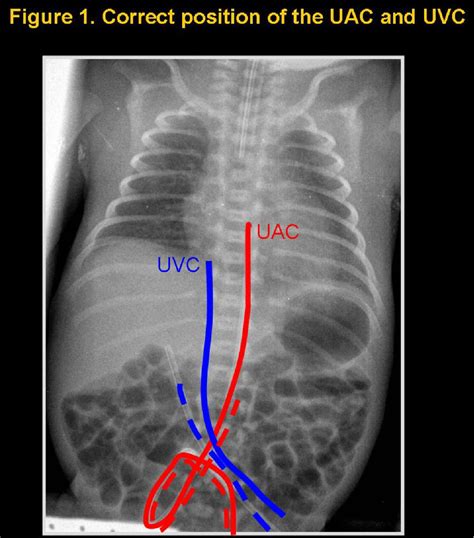

3. Insertion: The catheter is gently inserted into the umbilical vein, which is identified by its larger size and bluish color compared to the arteries. The catheter is advanced until it reaches the desired position, typically confirmed by ultrasound or X-ray.

5. Verification: The position of the catheter is verified using imaging techniques to ensure it is correctly placed in the inferior vena cava.